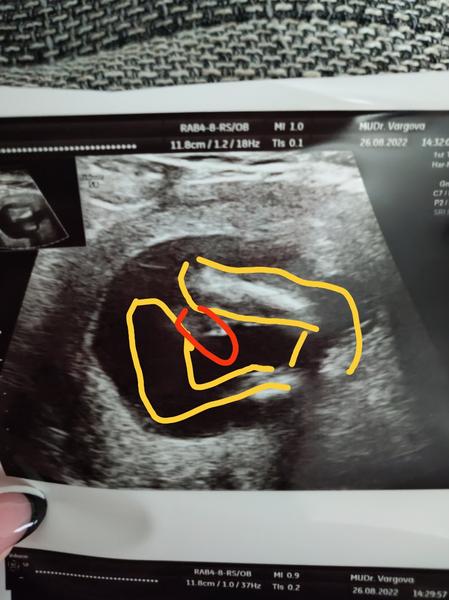

dnes 18tt hovorim ci sa nepozrie medzi nozky a ona ze zda.sa.ze.to vyzera.na babu.vravim ze fakt? Pred 2 tyzdnami ste vraveli ze ste.si na 90% ista.chlapcom a potom hladala a hladala a vravi ze sama nevie ze ona by povedala ze dievca ale ze.mozno toto je pindur (foto+ dalsie kde som znazornila nohy a cervenym to na co sa pytam) ze odspodu je tak vidno ritku a akoby sedelo v tureckom sede stehna a v strede cos male biele....

Z tejto fotky by som povedala, ze to stale moze byt jedno aj druhe...